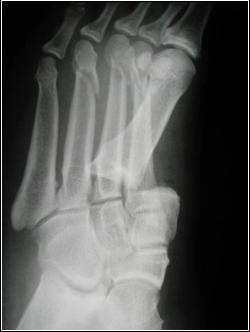

Dislocations